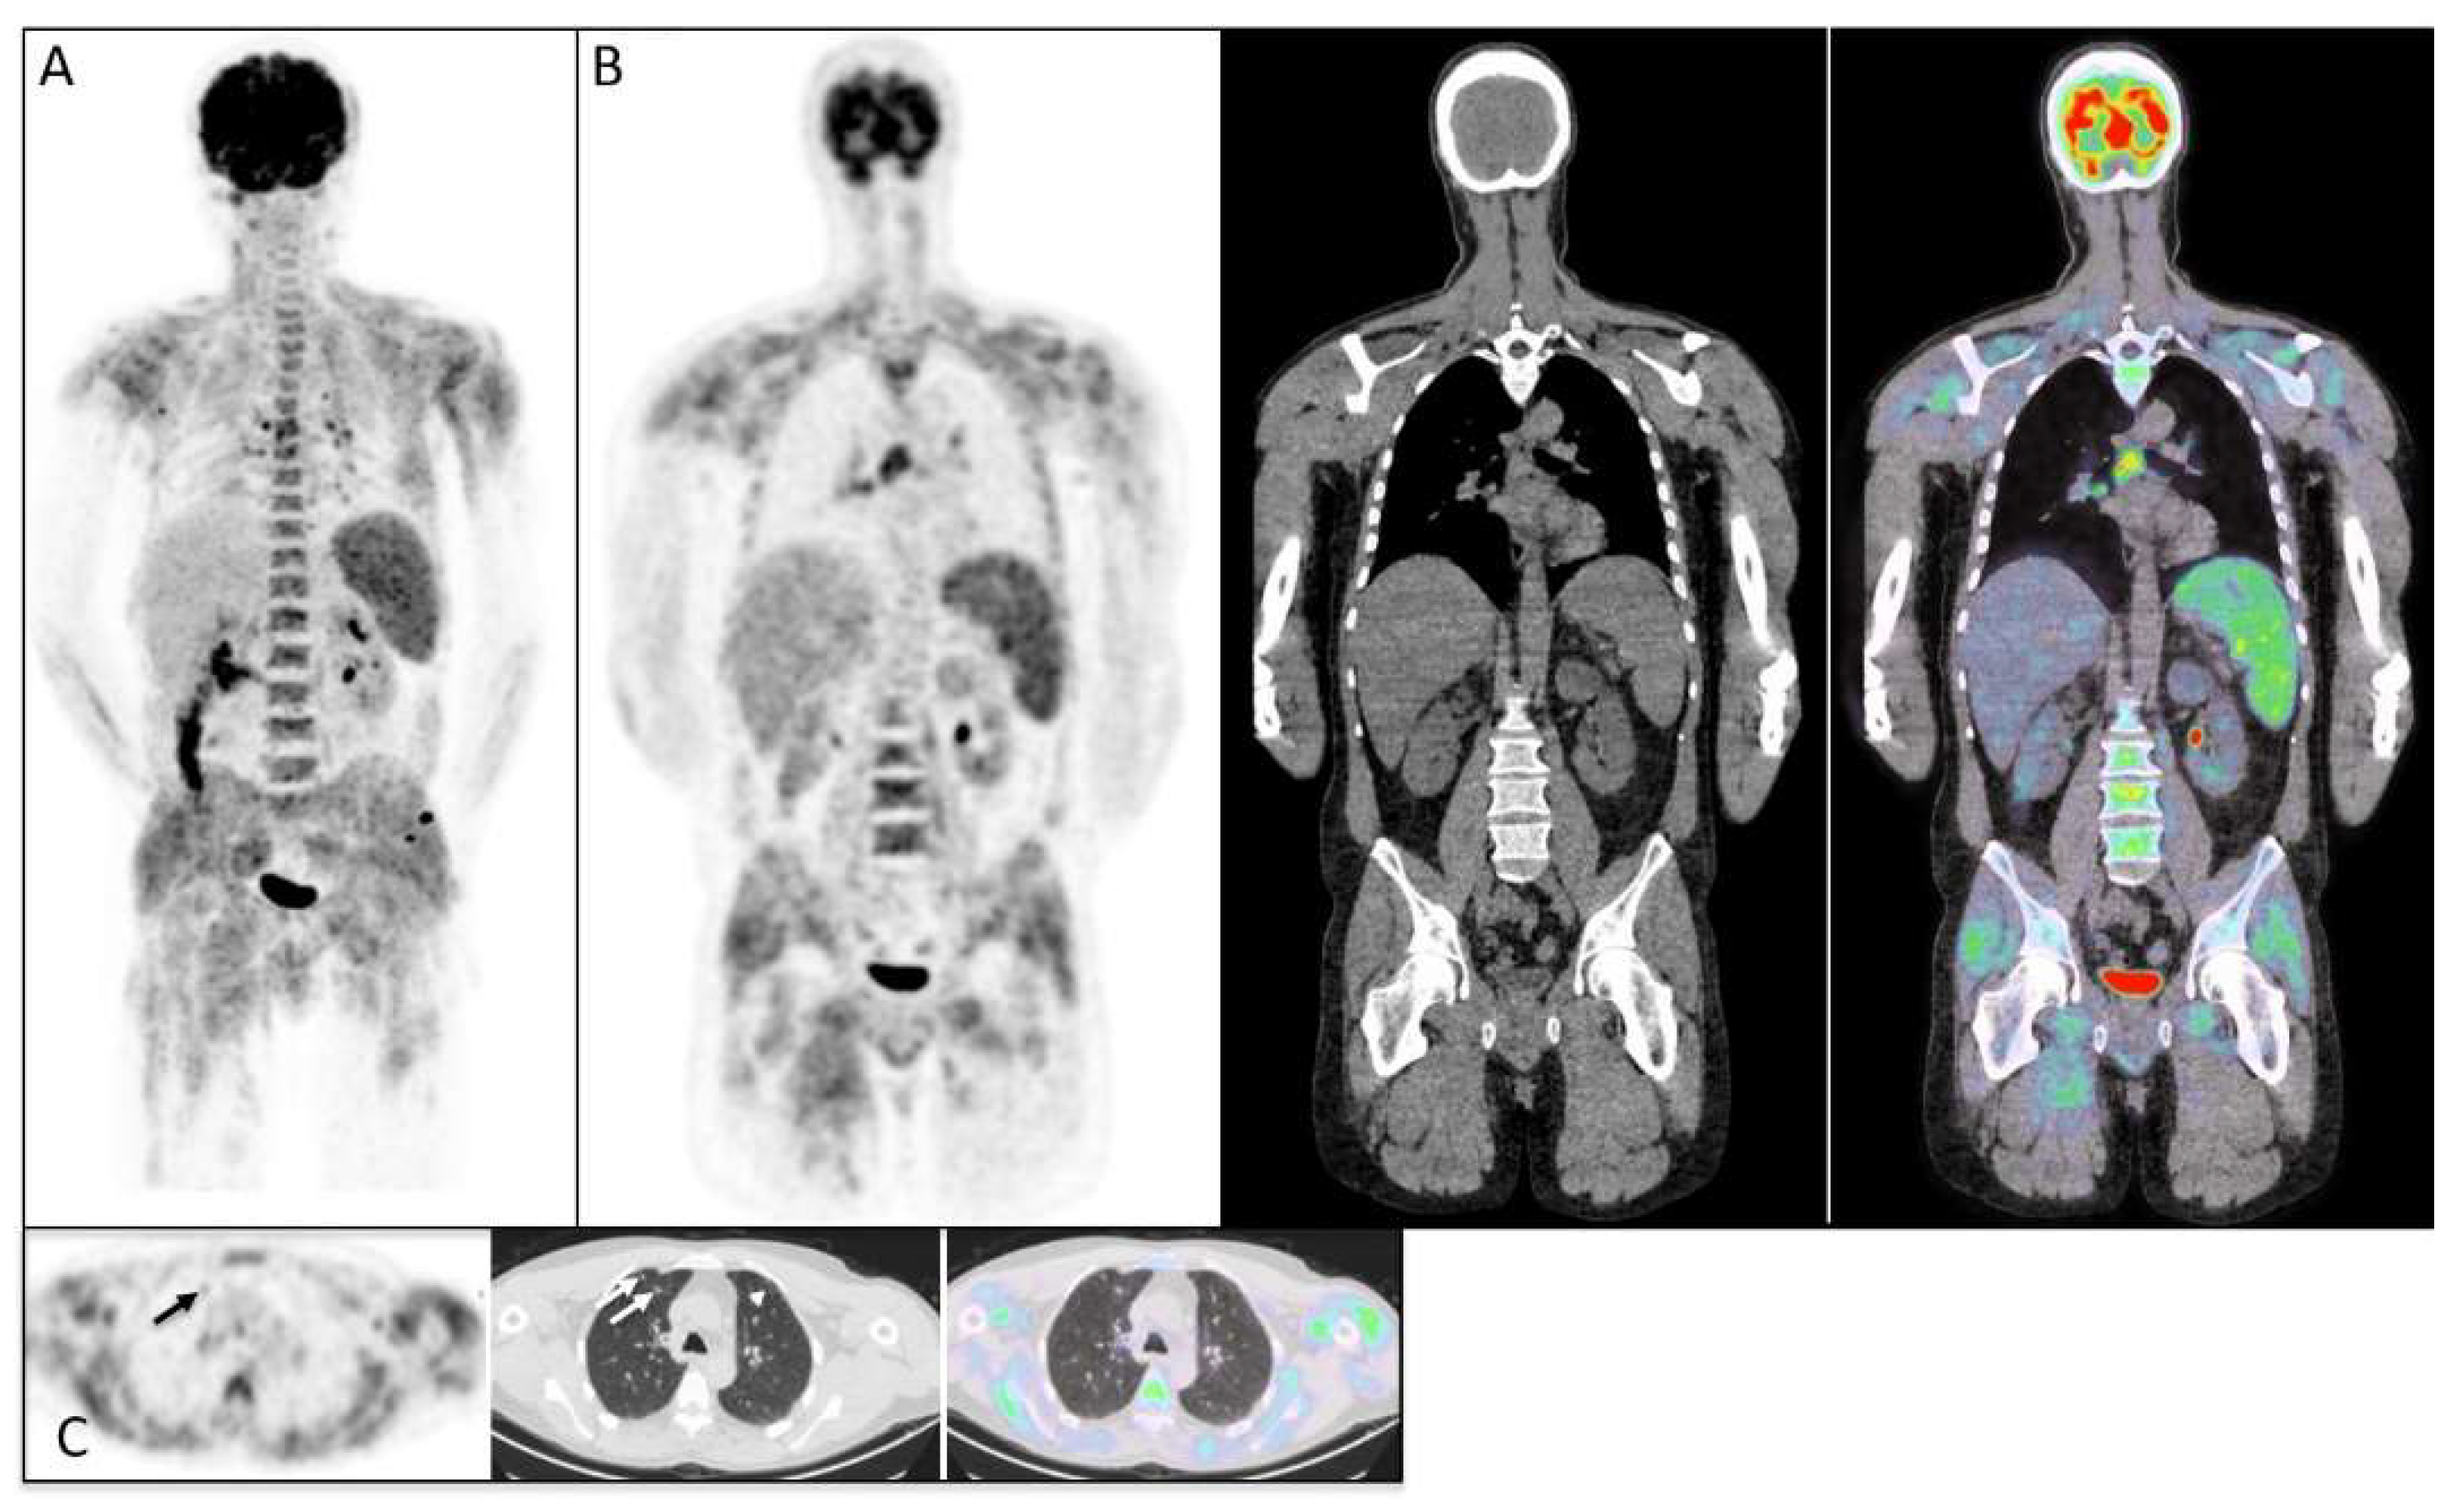

| Muscle activity on [18F]FDG-PET/CT | 13/27 (48.1%) |

| Interstitial lung diseases | 8 (27.5%) |

| Cancer detected by [18F]FDG-PET/CT | 3/27 (11.1%) |